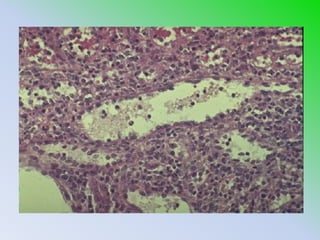

El documento habla sobre la histología del bazo. El bazo es un órgano linfoide ubicado en la cavidad abdominal izquierda que filtra la sangre y elimina glóbulos rojos viejos. Contiene vasos sanguíneos, linfocitos y macrófagos que ayudan al sistema inmune.